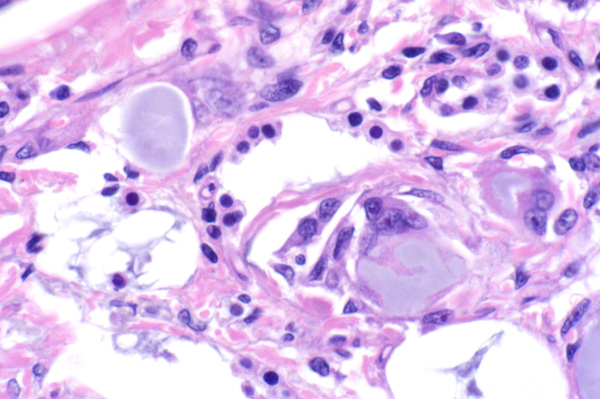

| 40x   |   Hematoxylin and Eosin | ||||

Multinucleated cells surround amorphous material. There is type II pneumocyte hyperplasia (arrows).